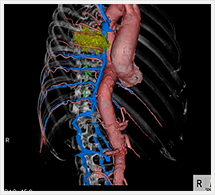

画像紹介

CTでは輪切り像の他にも立体的な画像(3D画像)を作成することもできます。そのためにはより細かくキレイな画像を撮影しなければなりません。当院では64列CTを導入しており、キレイな画像をより細かく撮影することができます。その画像を元に3D画像を作成することによって、より正確な手術のシミュレーションが可能になります。実際に手術をしたときの様子が、手術をする前に画像として見らます。外科系の手術には欠かせない技術となっておりますが、内科系でも血管内手術にも多く利用されております。

当診療放射線技術科では毎日各診療科に対して、その手術に最適な3D画像を提供しております。

以下にその3D画像を一部分紹介します。

胸部大動脈

胸部大動脈(赤)、奇静脈(青)、脊椎結核(黄)